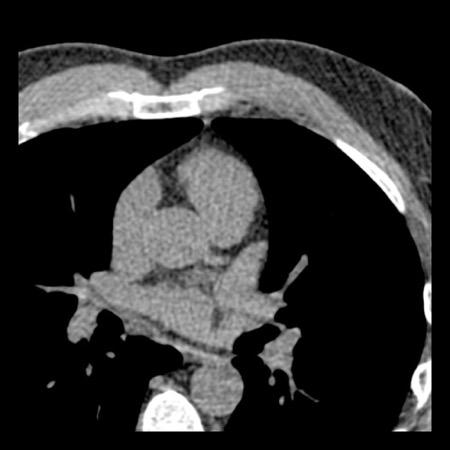

case 4 – CAD-RADS 3/P1/I+ thrombus left ventricle

First, scroll through the CTA images.

How would you describe the findings on the coronary CTA?

The findings are:

- Moderate (50-69%)

stenosis in the proximal LAD caused by a non-calcified plaque. - Variant of

sinoatrial (SA) nodal artery. The artery usually arises from the RCA as a second

branch after the conus artery, however in this case it arises from the LCX,

courses behind the aorta, anastomosing with the right atrium and with a small

branch supplies the SA-node of the heart. - Thrombus in the

apex of the left ventricle. - CTP was performed

in this patient. CTP showed a perfusion defect at stress imaging in the

territory of the LAD (I+), at rest no perfusion defect was visible.

This patient classifies as CAD-RADS 3/P1/I+, which means

this patient requires further investigation.